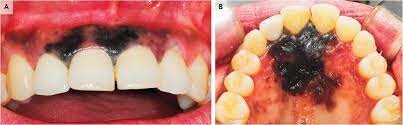

What Causes a Black Spot on Your Gums?

First, we recommend taking a moment to breathe and relax. According to the Oral Cancer Foundation, dark spots rarely indicate a serious condition like cancer and are usually benign. Spots in the mouth are often not fully black but may appear that way as they can be hard to see. We’re here to help walk you through the causes of dark spots in your mouth and what they mean.

Oral conditions like dark spots on your gums have various causes and can be challenging to diagnose. These spots can either be harmless or the result of an underlying disease, so it's essential to speak to your doctor if you believe you have any symptoms.

In rare cases, benign lesions that don't require treatment may transform into oral malignant melanoma, a type of oral cancer. A doctor will look at a range of factors to see if the lesion qualifies as melanoma. According to a research article published in the Journal of Indian Academy of Oral Medicine and Radiology, melanoma constitutes only 3–5% of all cutaneous malignancies, and oral melanoma is an aggressive neoplasm which accounts for less than 0.5%.